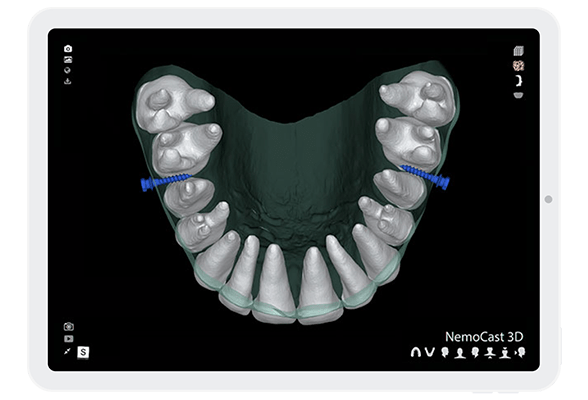

- High precision with micro-screws

Plan treatments with micro-screws for skeletal anchorage to enhance your orthodontic treatments. Design the guide to place them.